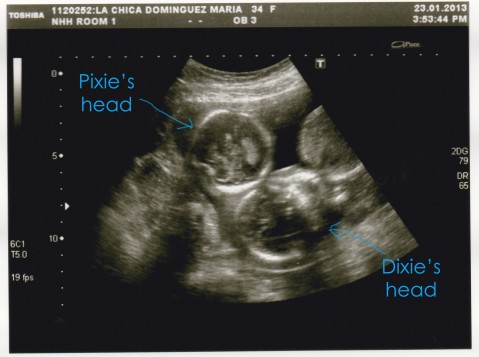

Here are the pictures that we got yesterday:

And this is somehow both of them together…